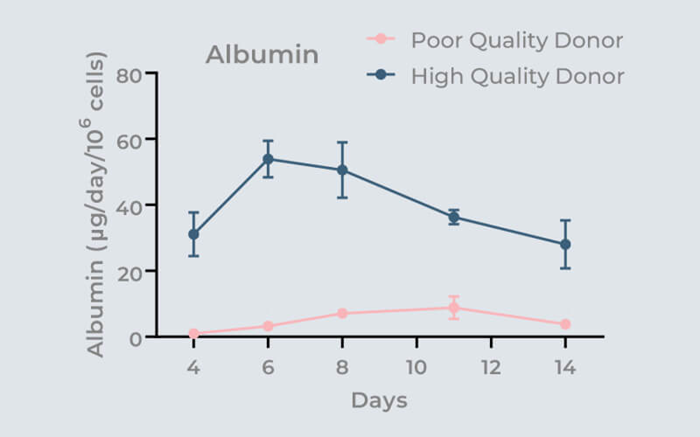

The effect of donor quality over 14 days on microtissue functionality (albumin production) is highlighted in the graph. By utilizing 3D-validated cells, the possibility of subpar assay performance is eliminated.

Image Credit: CN-Bio